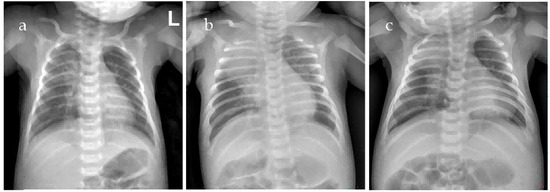

Severe Pertussis During Early Infancy from a High-Altitude Region: Two Clinical Cases and Literature Review

Objective: To investigate how the high-altitude environment modifies severe pertussis in young infants and analyze its pathophysiological mechanisms and clinical management implications. Methods: Clinical data of two young infants with severe pertussis residing at 3650 m were retrospectively analyzed, including presentation, laboratory findings, pathogen detection, treatment, and outcomes. A literature review explored synergistic interactions between high-altitude factors and pertussis pathophysiology. Results: Case 1 had macrolide-resistant Bordetella pertussis (MRBP, 23S rRNA A2047G) with peak WBC 52.25 × 109/L, and received cefoperazone-sulbactam, piperacillin-tazobactam and azithromycin, and was successfully treated with trimethoprim-sulfamethoxazole combined with exchange transfusion. Case 2 had Bordetella pertussis confirmed by PCR with peak WBC 36.55 × 109/L, receiving cefoperazone-sulbactam and azithromycin, and recovered. Both developed respiratory failure requiring non-invasive ventilation and survived without pulmonary hypertension. High-altitude stressors—hypoxia, enhanced pulmonary vascular reactivity, and hypercoagulability—synergize with pertussis-induced hyperleukocytosis as a “dual hit,” accelerating cardiopulmonary deterioration and elevating thrombotic risks. Conclusions: High altitude is an independent risk modifier in infantile pertussis, demanding heightened vigilance and proactive interventions: early non-invasive ventilation, prophylactic anticoagulation, and timely exchange transfusion before pulmonary hypertension develops. This is the first high-altitude case series that provides essential insights for clinicians in similar environments globally, guiding early recognition and proactive management strategies to improve outcomes in this vulnerable population. Full article

Figure 1